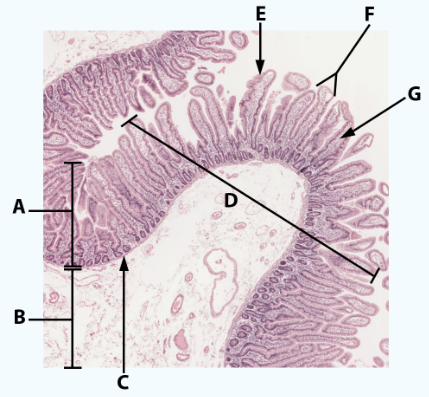

A

Mucosa

B

Muscularis mucosa

C

MALT

D

Lumen

E

Gastric pits: simple columnar epithelium

F

Gastric glands

G

Submucosa

H

Muscularis externa: oblique, circular, and longitudinal

area

Stomach

A

Mucosa: simple columnar epithelium with microvilli

B

Submucosa

C

muscularis mucosa

Area

Small intestine

E

simple columnar epithelium with goblet cells and microvilli

F

Villi

G

Lamina propria